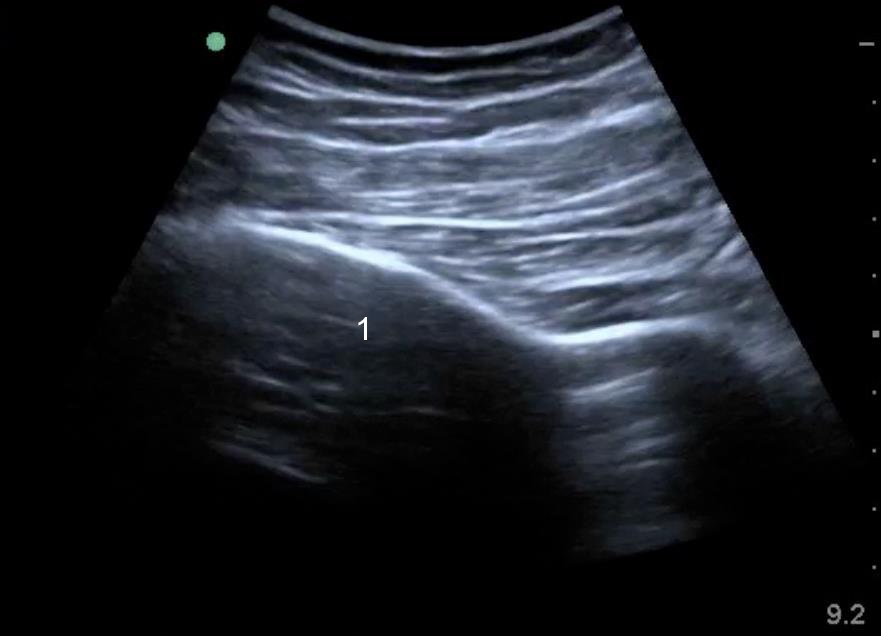

Imagen 1 de la estructura ósea de la parte posterior de la cadera

Ilion